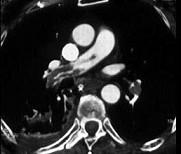

问题 女性,50岁。因肺炎入院,抗炎3天体温仍未退,呼吸困难,痰中带血,伴胸痛,右下肢肿胀(胸部CT见图)。最可能的疾病是 ( )

选项 A.肺血栓栓塞症 B.冠状动脉硬化性心脏病 C.原发性肺动脉高压 D.肺炎 E.肺结核

答案 A